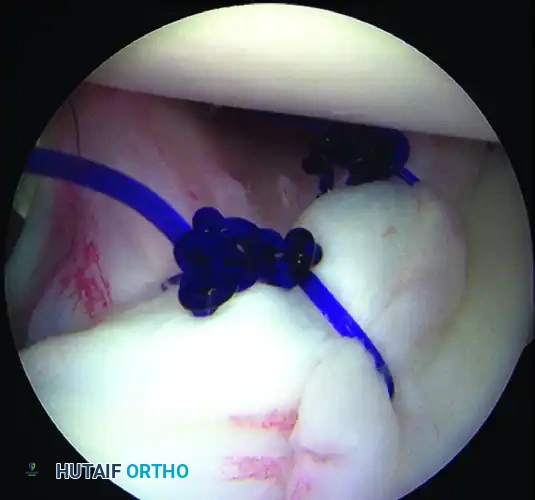

5. Recreating the Anterior Bumper

Proceed superiorly, placing the second and third double-loaded anchors. Firmly secure the sutures, compressing the capsuloligamentous complex to the abraded bone surface. This "loop and knot fixation" rolls the tissue up onto the glenoid face, recreating a robust anterior soft-tissue bumper.

D, Knots tied re-creating soft tissue bumper.

B, Restored anterior labral bumper (arthroscopic view).

C, Restored anterior labral bumper (alternate angle).